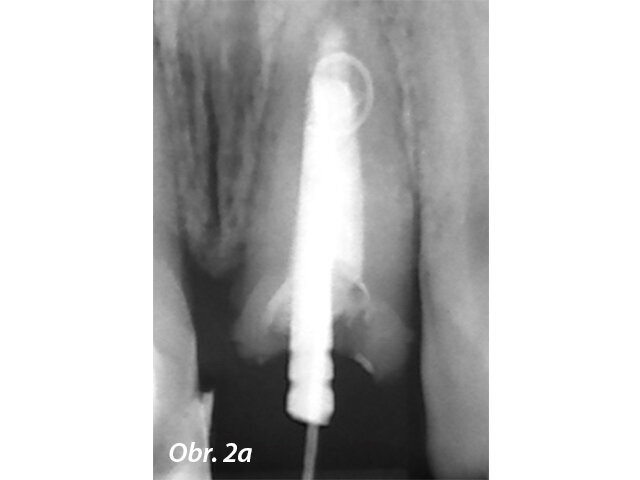

Aby se zabránilo přetlačení výplňového materiálu u zubů s nedokončeným vývojem, používá se MTA jako apikální zátka. Výsledky mnoha studií ukazují, že MTA podporuje tvorbu tvrdých tkání více a je spojeno s menším počtem zánětlivých reakcí než jiné testované materiály (Simon a spol. 2007) (obr. 2a–g).

Endodonticky ošetřený zub s píštělí

Po reendodoncii se ukázal otevřený apex

Aplikace PD MTA White s MAP systémem

Kondenzace MTA papírovým čepem

Postoperační RTG ukazuje výplň MTA a rekonstrukci se světlovodným čepem